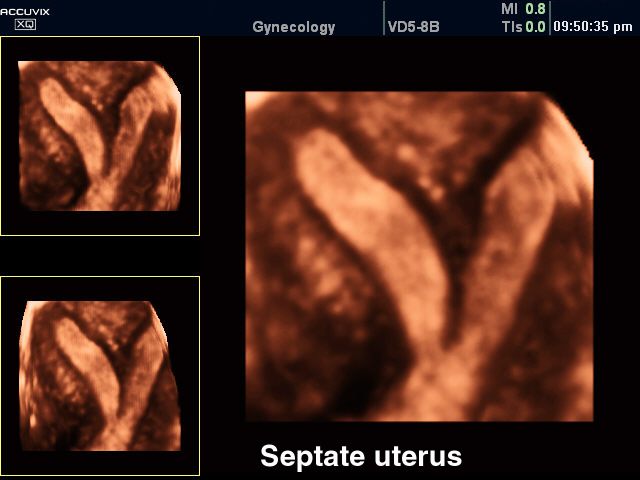

Варианты двурогой матки

3-хмерное УЗИ при двурогой матке

Седловидная матка является частным проявлением двурогой матки. При седловидной матке на наружной поверхности дна органа образуется небольшое вогнутое углубление в виде седла. В гинекологии из общего числа аномалий развития матки на долю седловидной матки приходится около 23% случаев. Степень расщепления дна матки на два рога бывает различной: расширение поперечного размера, уплощение дна, слабое расхождение дна на два рога. Во всех случаях форма матки в разрезе напоминает седло.

В процессе эхографии малого таза (УЗИ) седловидная матка выявляется не всегда. При значительной деформации поперечное сканирование позволяет выявить увеличение ширины дна матки до 68 утолщение миометрия стенки дна до 10-14 мм и его выбухание в полость органа. Для обнаружения седловидной матки УЗИ предпочтительнее проводить влагалищным датчиком во вторую фазу цикла при достаточно выраженной толщине эндометрия.